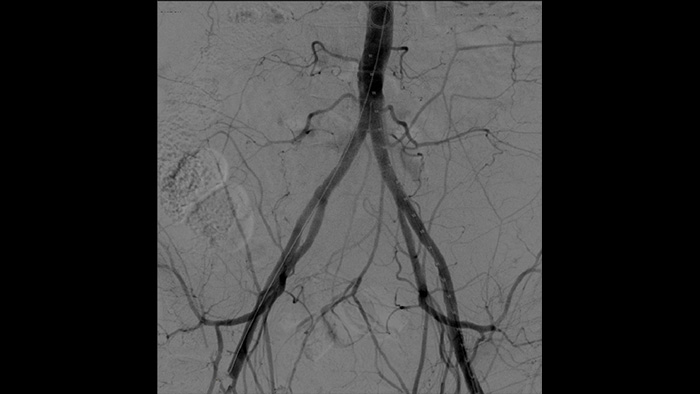

La angiografía por sustracción digital (ASD) se utiliza en procedimientos vasculares intervencionistas para ver con claridad los vasos sanguíneos mediante la eliminación de estructuras que pueden oscurecer la visibilidad de los vasos. La hoja de ruta de fluoroscopia superpone la imagen de contraste sustraída con anterioridad adquirida en la fluoroscopia en vivo, lo que le permite rastrear el dispositivo sin reinyectar el contraste.

Con Zenition, nuestra calidad de imagen de la ASD ha mejorado mucho. Ya no vemos una imagen granulada. Solo una imagen muy clara.

Dr. Ramón Vila Coll

Hospital Universitario de Bellvitge. Barcelona